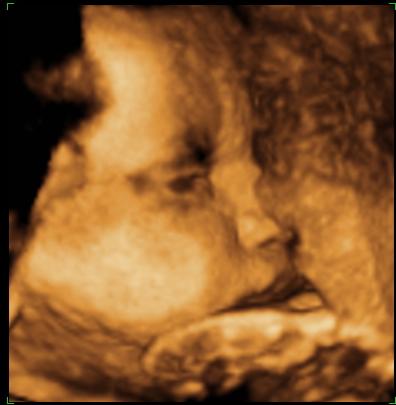

A második képen nyitva van a szeme is